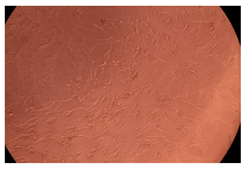

The results of the cytotoxicity assay, given in Figure 5, indicate that the tested PMs at all three established concentrations (10, 50, and 100 µg/mL) did not show cytotoxic effects on fibroblast cells at either 24 or 48 h after incubation. The percentages of cell viability were high, over 90%, in cells that were exposed to a concentration of 10 µg/mL for 24 h for all tested materials. Even at 48 h after incubation, the percentage of cell viability was as high as 90.4% in cells exposed to a concentration of 10 µg/mL for the Cop B sample. For both drug-loaded PMs, the cell viability decreased slightly at all tested concentrations. It also appears that the Dorzolamide-loaded PMs have slightly lower cell viability as compared to IMC-loaded PMs. Micrographs of the fibroblast cells after incubation times of 24 and 48 h are provided in Table 2.

Table 2.

Micrographs of fibroblast cells after 24 and 48 h incubation times, respectively.

As the cell viability values are all over 80%, the results indicate that the PMs, at the established concentrations, can be used successfully for in vivo biomedical applications.